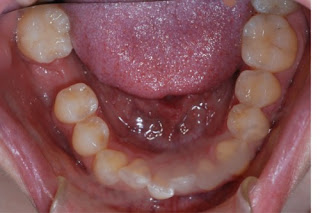

カテゴリ:カテゴリ未分類 Gãy răng có mọc lại không ? Răng là bộ phận khá đặc biệt trên cơ thể. Bởi một khi đã bị mất đi, dù chỉ là mất một phần của răng thì cũng không thể tự hồi phục lại như cũ được.  →http://cayrangimplant.com.vn/gia-trong-tru-rang-khi-mat-rang-hoan-toan-la-bao-nhieu/ →http://cayrangimplant.com.vn/gay-chan-rang-co-moc-lai-khong/ Răng vĩnh viễn có mọc lại không? Độ tuổi thay và mọc răng vĩnh viễn của con người là từ 6 -12 tuổi, khi này, bạn sẽ có 28 chiếc răng, sau tuổi này nếu răng gãy sẽ không có bất kỳ răng nào mọc thay thế. Những chiếc răng mọc ở tuổi trưởng thành được gọi là răng khôn (răng số 8) mọc trong cùng của cung hàm, nếu mọc đủ 4 răng khôn thì hàm răng của bạn sẽ có tổng cộng 32 chiếc răng. Nếu bạn bị mất răng và ảnh hưởng không nhỏ đến việc ăn uống thì tốt nhất nên tìm hướng phục hồi lại răng bằng các cách trồng răng. Hơn thế nữa, răng nào cũng là chiếc răng đóng vai trò quan trọng, quyết định đến tính thẩm mỹ. Đây cũng là lời khuyên của các bác sỹ phục hình cho tất cả các trường hợp mất răng dù là ở vị trí nào trên cung hàm. Bởi vì, việc trồng lại răng không chỉ có tác dụng phục hồi thẩm mỹ mà còn để thực hiện chức năng ăn nhai. Đặc biệt hơn là nhằm duy trì sự ổn định của cấu trúc răng so với xương hàm, tránh hiện tượng tiêu xương do trống chân răng về sau. →http://cayrangimplant.com.vn/giai-phap-trong-rang-cho-truong-hop-mat-rang/ Trồng lại răng bị gãy chân răng bằng cách nào theo tư vấn của nha sĩ? – Làm răng tháo lắp: Là hình thức dùng chiếc răng giả gắn trên khung thép cố định vào các răng kế cận để giữ răng giả ổn định tại vị trí mất răng. Làm răng theo cách này rẻ hơn nhưng lại không bền. – Làm cầu răng: Đây là cách trồng răng tạo ra các chụp răng sứ để đồng thời thay thế cho răng bị mất và chụp lên hai răng kế cận hai bên khoảng trống mất răng. Cách này bền chắc và độ thẩm mỹ rất cao, răng đẹp và tự nhiên nhưng sẽ phải dùng đến số thân răng sứ nhiều hơn răng mất và còn phải mài 2 chiếc răng khỏe 2 bên thành cùi nhỏ. – Cấy ghép răng Implant: Implant răng là gì? Hướng khôi phục răng mất này là tối ưu nhất cho trường hợp gãy răng cấm, gãy chân răng vì có thể trồng lại răng rất bền chắc cả thân và chân răng, tuổi thọ duy trì dài lâu. Răng sẽ hỗ trợ chức năng ăn nhai rất tốt, không kém răng cấm thật, độ thẩm mỹ cũng tương đối cao, tự nhiên Ưu điểm đặc biệt của cấy răng Implant thay thế được cả chân răng và thân răng, không xâm lấn hay làm ảnh hưởng đến các răng kế cận, phục hồi chức năng ăn nhai, tính thẩm mỹ và duy trì vĩnh viễn trên cung hàm. Ngoài ra, nếu muốn tìm hiểu thêm về vấn đề gãy răng có mọc lại không bạn có thể liên hệ với Nha khoa KIM theo hotline 1900.6899 các bác sĩ luôn sẵn sàng giải đáp 24/24. お気に入りの記事を「いいね!」で応援しよう いいね!0 TWITTER シェアする 最終更新日 2017.06.26 16:06:43 コメント(0) | コメントを書く